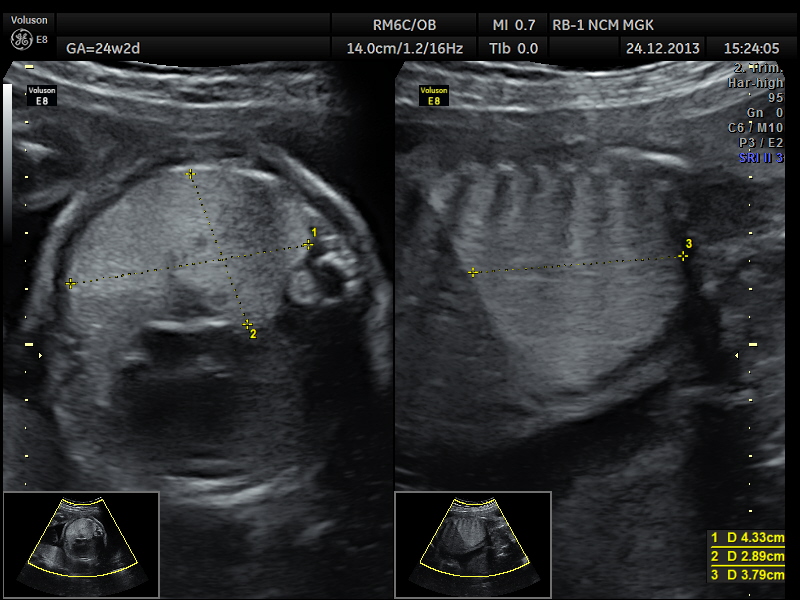

Вопрос 1

Поставьте диагноз

- А — норма;

- Б — гастрошизис;

- В — омфалоцеле;

- Г — экстрофия мочевого пузыря

Комментарий к ответу 1

Отчетливо определяется образование, исходящее из передней брюшной стенки, округлой формы с четким округлым контуром, мочевой пузырь виден в типичном месте, что позволяет исключить его экстрофию. Для гастрошизиса характерны неровные контуры образования. Содержимое образования имеет разную эхогенность: петли кишечника более высокой эхогенности, гипоэхогенная часть печени и анэхогенный желчный пузырь